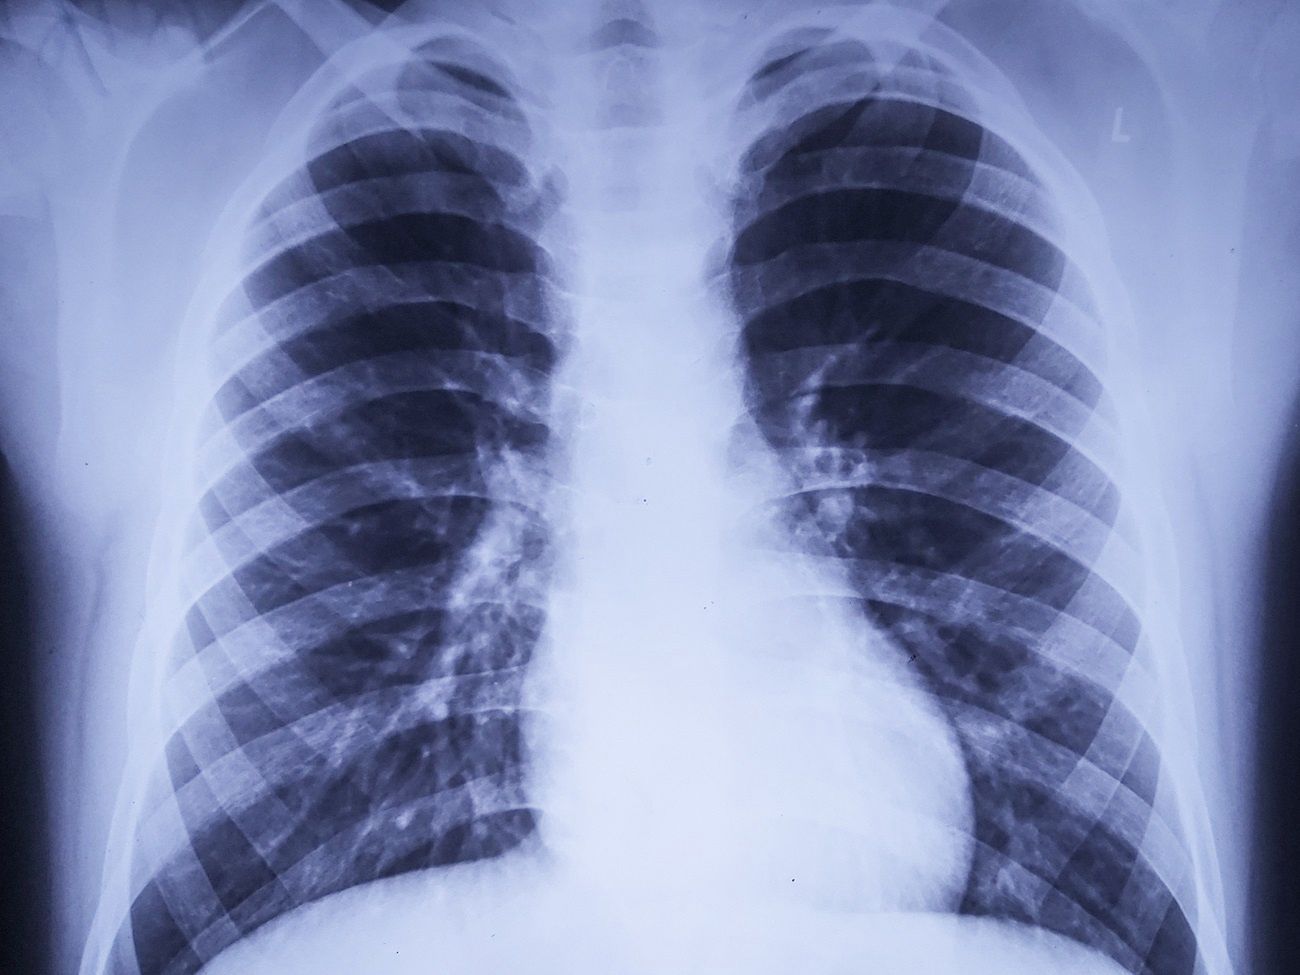

Tak Koronawirus Wplywa Na Pluca Zdjecie Chorej Pacjentki

Uszkodzenia Pluc U Pacjenta Z Koronawirusem Na Filmie 3d Dziennik Naukowy